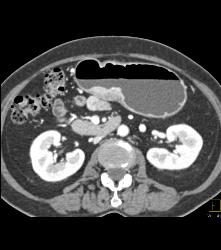

Antral Carcinoma